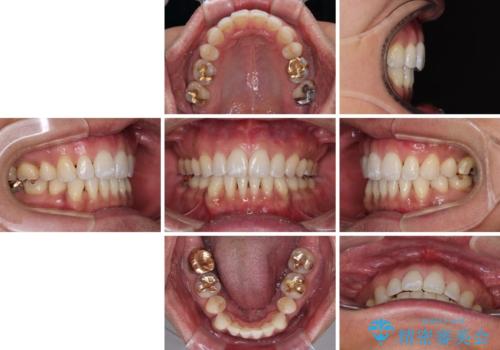

- 口元の突出感を気にして来院された患者様です。

強い咬合力と上顎前歯の傾斜により前歯が突出し、唇が閉じにくい状況であったため、上下左右の第一小臼歯4本を抜歯し、ワイヤー装置にて矯正治療を行うこととしました。

非常に咬合力が強いため、抜歯したスペースが閉じるのか不安でしたが、順調に歯が移動し、予定よりも早く治療を終えることができました。